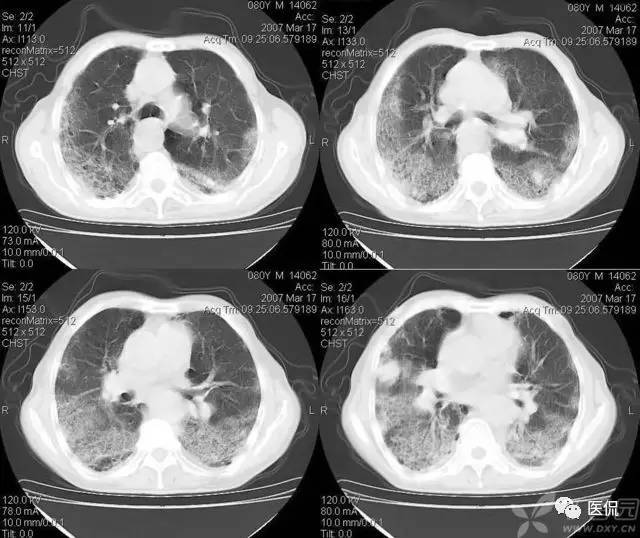

粘液支气管征又称为支气管液像,支气管粘液栓塞导致的CT征象。其病理基础是肺不张内有支气管粘液栓塞。由支气管狭窄梗阻、粘液分泌异常和纤毛活动障碍所致。对于中央型肺癌、狭窄或梗阻支气管的远端形成粘液铸型。支气管内膜结核有较长范围的支气管狭窄及支气管纤毛破坏使粘液不易排出。支气管分泌物增多也对粘液潴留起重要作用。慢性肺炎的支气管分泌物增多、粘稠及纤毛破坏是支气管粘液潴留的原因。CT增强扫描0表现为肺不张内未强化的管状或结节状低密度影,与支气管走行方向一致。

图1 变态反应性支气管肺曲霉菌病患者经治疗后右上肺浸润性病变大部分吸收。CT片上可见到树枝状粘液栓,其主轴指向肺门并与支气管的走向分布一致。支气管可见明显扩张 图2 左上肺肺癌患者,经细胞学检查证实。CT示肿瘤突入左主支气管,可见杯口状表现。其远端分支状支气管粘液栓清晰可见,轴向指向肺门。图3,4 支气管扩张患者反复多次咯出棒状和粉皮状粘液栓。CT示左下叶背段粘液栓,支气管也明显扩张(图3)。同一患者当粘液栓咯出后CT片可见扩张的支气管中间呈透亮带,横径比原粘液栓稍小,酷似鱼嘴状(图4)。

左图:治疗前的支气管粘液栓; 右图:治疗后粘液栓吸收,支气管通畅